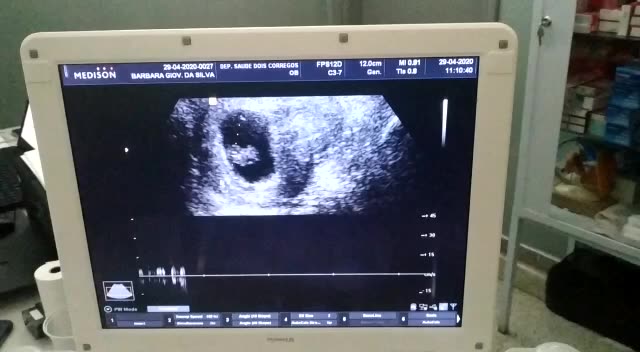

🤰🏻 1° ultrassom 😍 As maravilhas de ser mãe pela primeira vez, os desafios de uma nova jornada que apenas se inicia.Agora, batem dois corações em meu corpo.